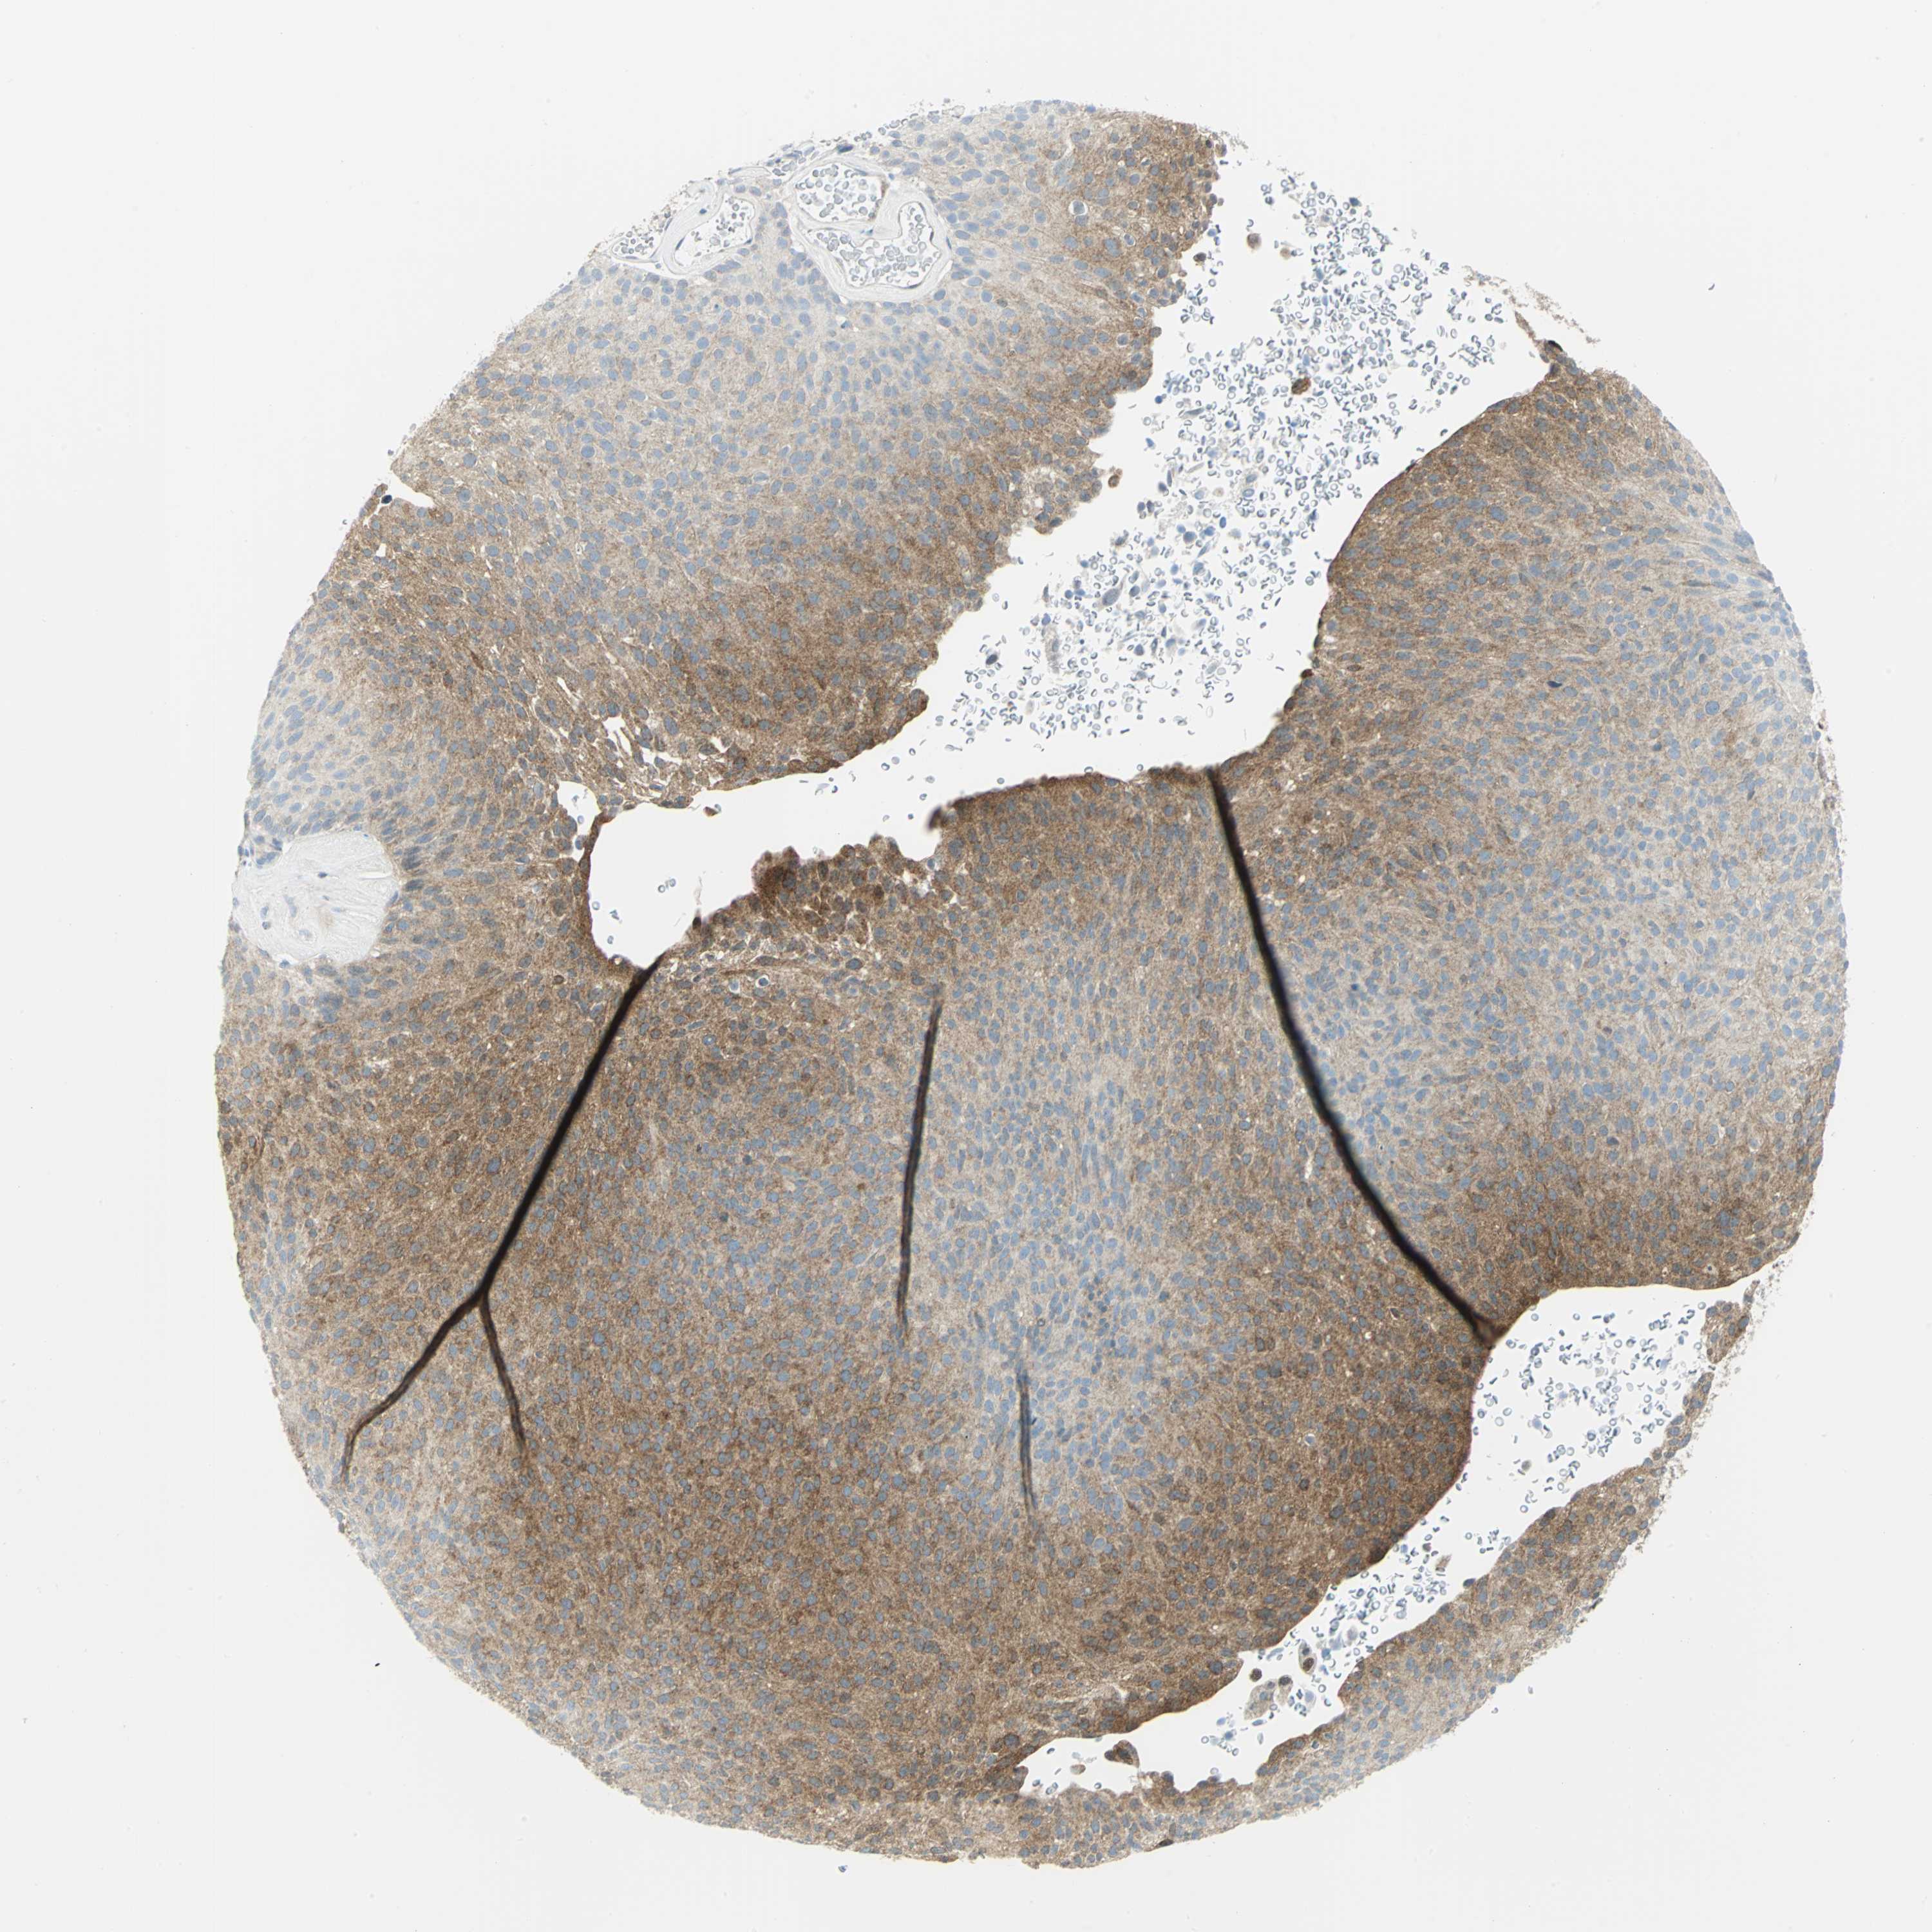

UROTHELIAL CANCER - Protein expressioni

A mouse-over function shows sample information and annotation data. Click on an image to view it in a full screen mode. Samples can be filtered based on level of antibody staining by selecting one or several of the following categories: high, medium, low and not detected. The assay and annotation is described here.

Antibody stainingi

Antibody staining in the annotated cell types in the current human tissue is reported as not detected, low, medium, or high, based on conventional immunohistochemistry profiling in selected tissues. This score is based on the combination of the staining intensity and fraction of stained cells.

Each image is clickable and will lead to virtual microscopy that enables deeper exploration of all samples and also displays staining intensity scores, fraction scores and subcellular localization as well as patient and tissue information for each sample.

Antibody HPA004177

Antibody CAB006252

Urothelial carcinoma, High grade

Urothelial carcinoma, Low grade